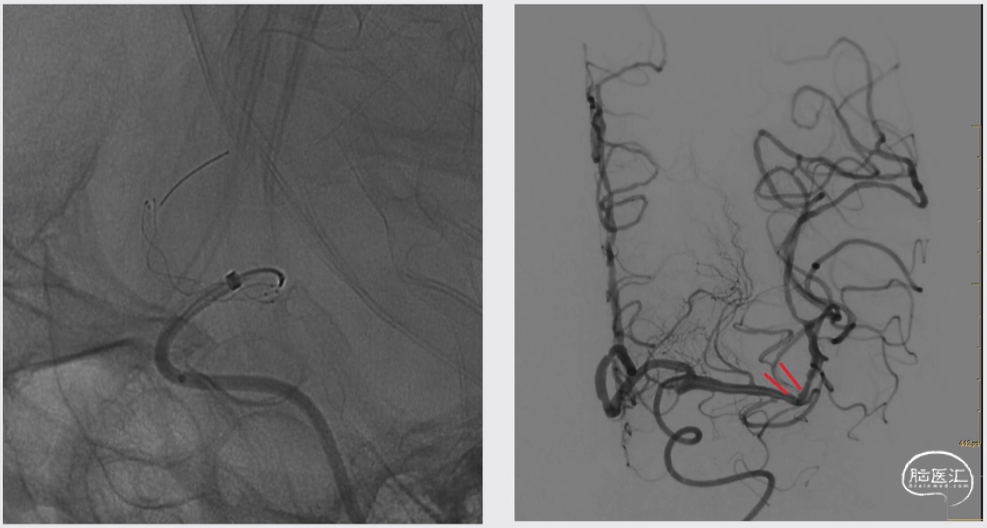

介入手术

术后

术后6小时CT:

右侧顶叶、基底节区与右侧额顶颞叶脑沟及外侧裂池高密度影,首先考虑对比剂外渗,未排合并出血

术后第一天:神志清,精神较差,GCS 13分,肌力肌张力正常

波立维75mg qd+甘油果糖氯化钠250ml bid+尼莫地平片30mg tid

术后第一天24小时CT:

右侧顶叶、基底节区与右侧额顶颞叶脑沟及外侧裂池高密度影,考虑为出血

术后第15天,来院门诊复诊CT

神志清,精神状态好,GCS 15分,肌力肌张力正常。